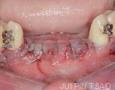

Surgery

1 Months

3 Months